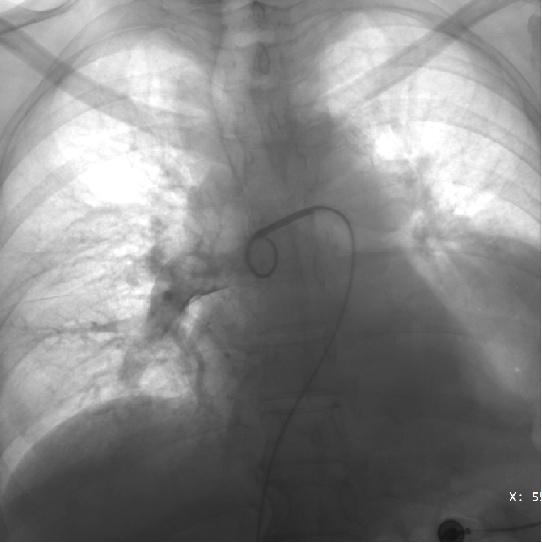

术后复查造影可见右肺动脉血栓消失,

轮廓正常,管腔也粗了